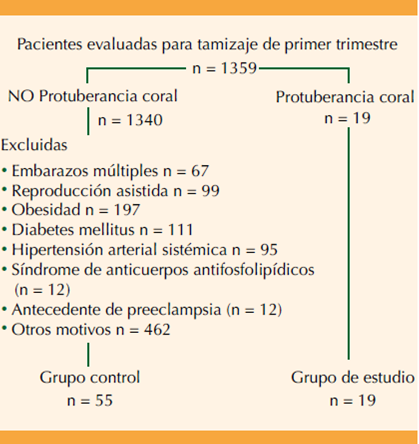

Estudio de cohorte prospectiva efectuado en pacientes referidas para tamizaje del primer trimestre a una unidad de Medicina y Cirugía Fetal de tercer nivel de referencia (Prenatalia Medicina Fetal San Javier, Guadalajara, Jalisco, México) de abril del 2019 a diciembre 2021. Criterio de inclusión: embarazos únicos con una medición de longitud cráneo-caudal comprendida entre 45 y 84 mm y que las madres dieran su consentimiento para participar en el estudio. El tamizaje del primer trimestre es parte de la evaluación rutinaria integral del embarazo.

Criterios de exclusión: embarazos múltiples, embarazos concebidos por fertilización in vitro o técnicas de reproducción asistida, obesidad materna (índice de masa corporal mayor de 30), antecedentes de enfermedad metabólica (diabetes mellitus tipos 1 o 2), cardiovascular (hipertensión arterial sistémica crónica o cardiopatía estructural), enfermedad autoinmunitaria (síndrome de anticuerpos antifosfolipídicos, lupus eritematoso y antecedentes personales o familiares (madre) de enfermedad placentaria (preeclampsia o restricción del crecimiento intrauterino).

Para el grupo control se consideraron 55 pacientes, luego de tomar en cuenta los criterios de exclusión. Figura 6

Primero: la población de estudio corresponde a una debidamente seleccionada y, a pesar de haber excluido los factores conocidos (Figura 6) la naturaleza observacional del estudio no permitió controlar el efecto de las variables desconocidas y confusoras potenciales. Por tanto, es posible considerar a la población de estudio de alto riesgo por el medio de referencia y por las características epidemiológicas de las pacientes y, con esto, que la probabilidad de un mal desenlace sea mayor al de la población general.